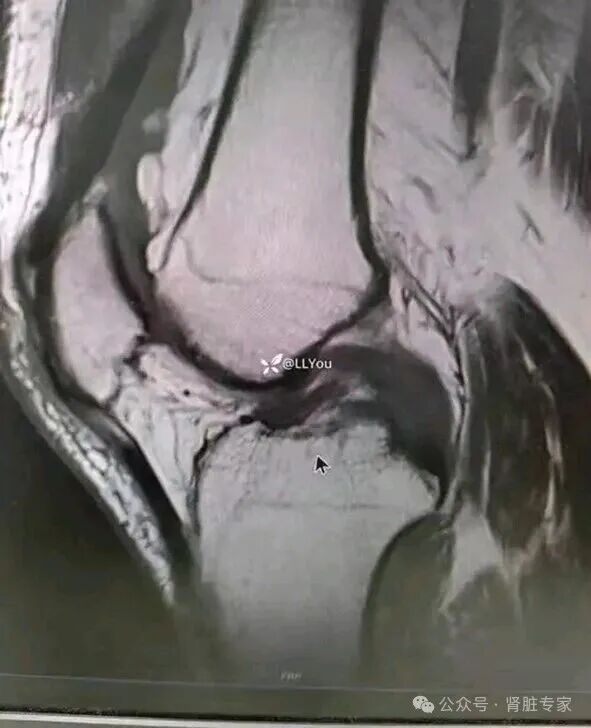

影像学检查‌:X线显示关节骨质疏松、间隙狭窄或畸形;